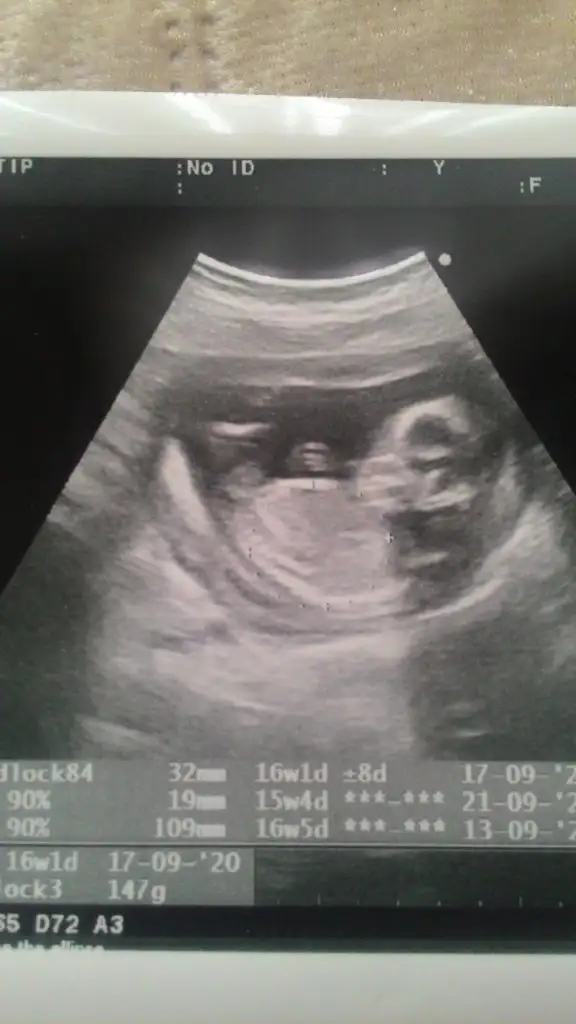

dr soylemeden siz gorun genital nub teorisi ( bebegin cinsiyeti)

Canımlar biliyorum biraz büyüdü bebegim ama yinede yorum yaparmisiniz